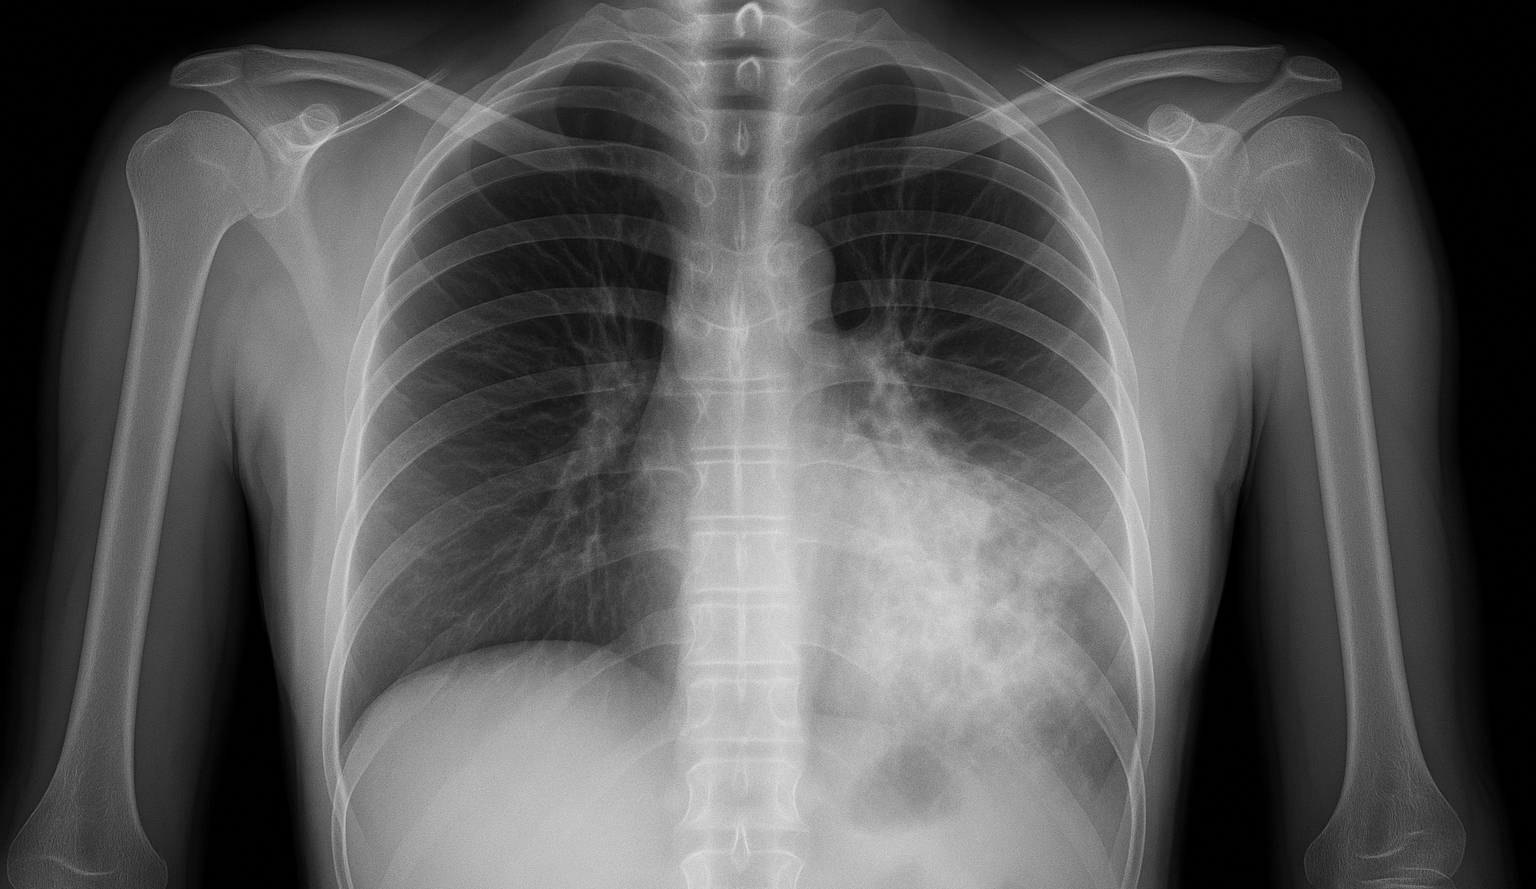

How to Diagnose Pneumonia?

Several examination and test were performed by doctors to confirm pneumonia:

- Chest X-ray to confirm infection.